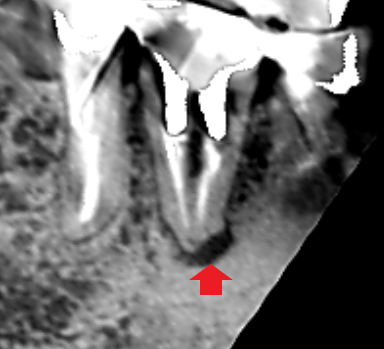

精密根管治療6カ月後の経過観察時の矢状断のCT画像です。下顎第一大臼歯の矢印の先にあった膿の影が消え、歯槽骨が再生しています。

精密根管治療6カ月後の経過観察時の冠状断のCT画像です。下顎第一大臼歯の根の舌側に拡がっていた長い膿の影が消え、歯槽骨が再生しています。膿の原因は、単なる根管治療不足でした。